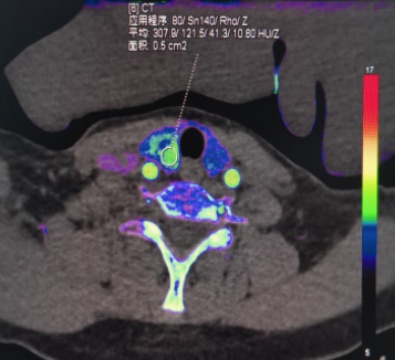

(a) (b) (c) (d)

(e) (f) (g) (h)

(e)~(h)结节性甲状腺肿患者双能量CT增强扫描动脉期原始图像、碘图、Rho/Z图及病理图

Figure 1. Examples of dual-energy CT arterial phase images, iodine uptake images, Rho/Z images, and pathological findings in three groups of patients with thyroid nodules (HE, ×100, H) (Rho/Z, Electron Density/Effective Atomic Number)

1. 三组甲状腺结节患者双能量CT动脉期图、碘图、Rho/Z图及病理图示例(HE, ×100, H) (Rho/Z,电子密度云/有效原子序数)